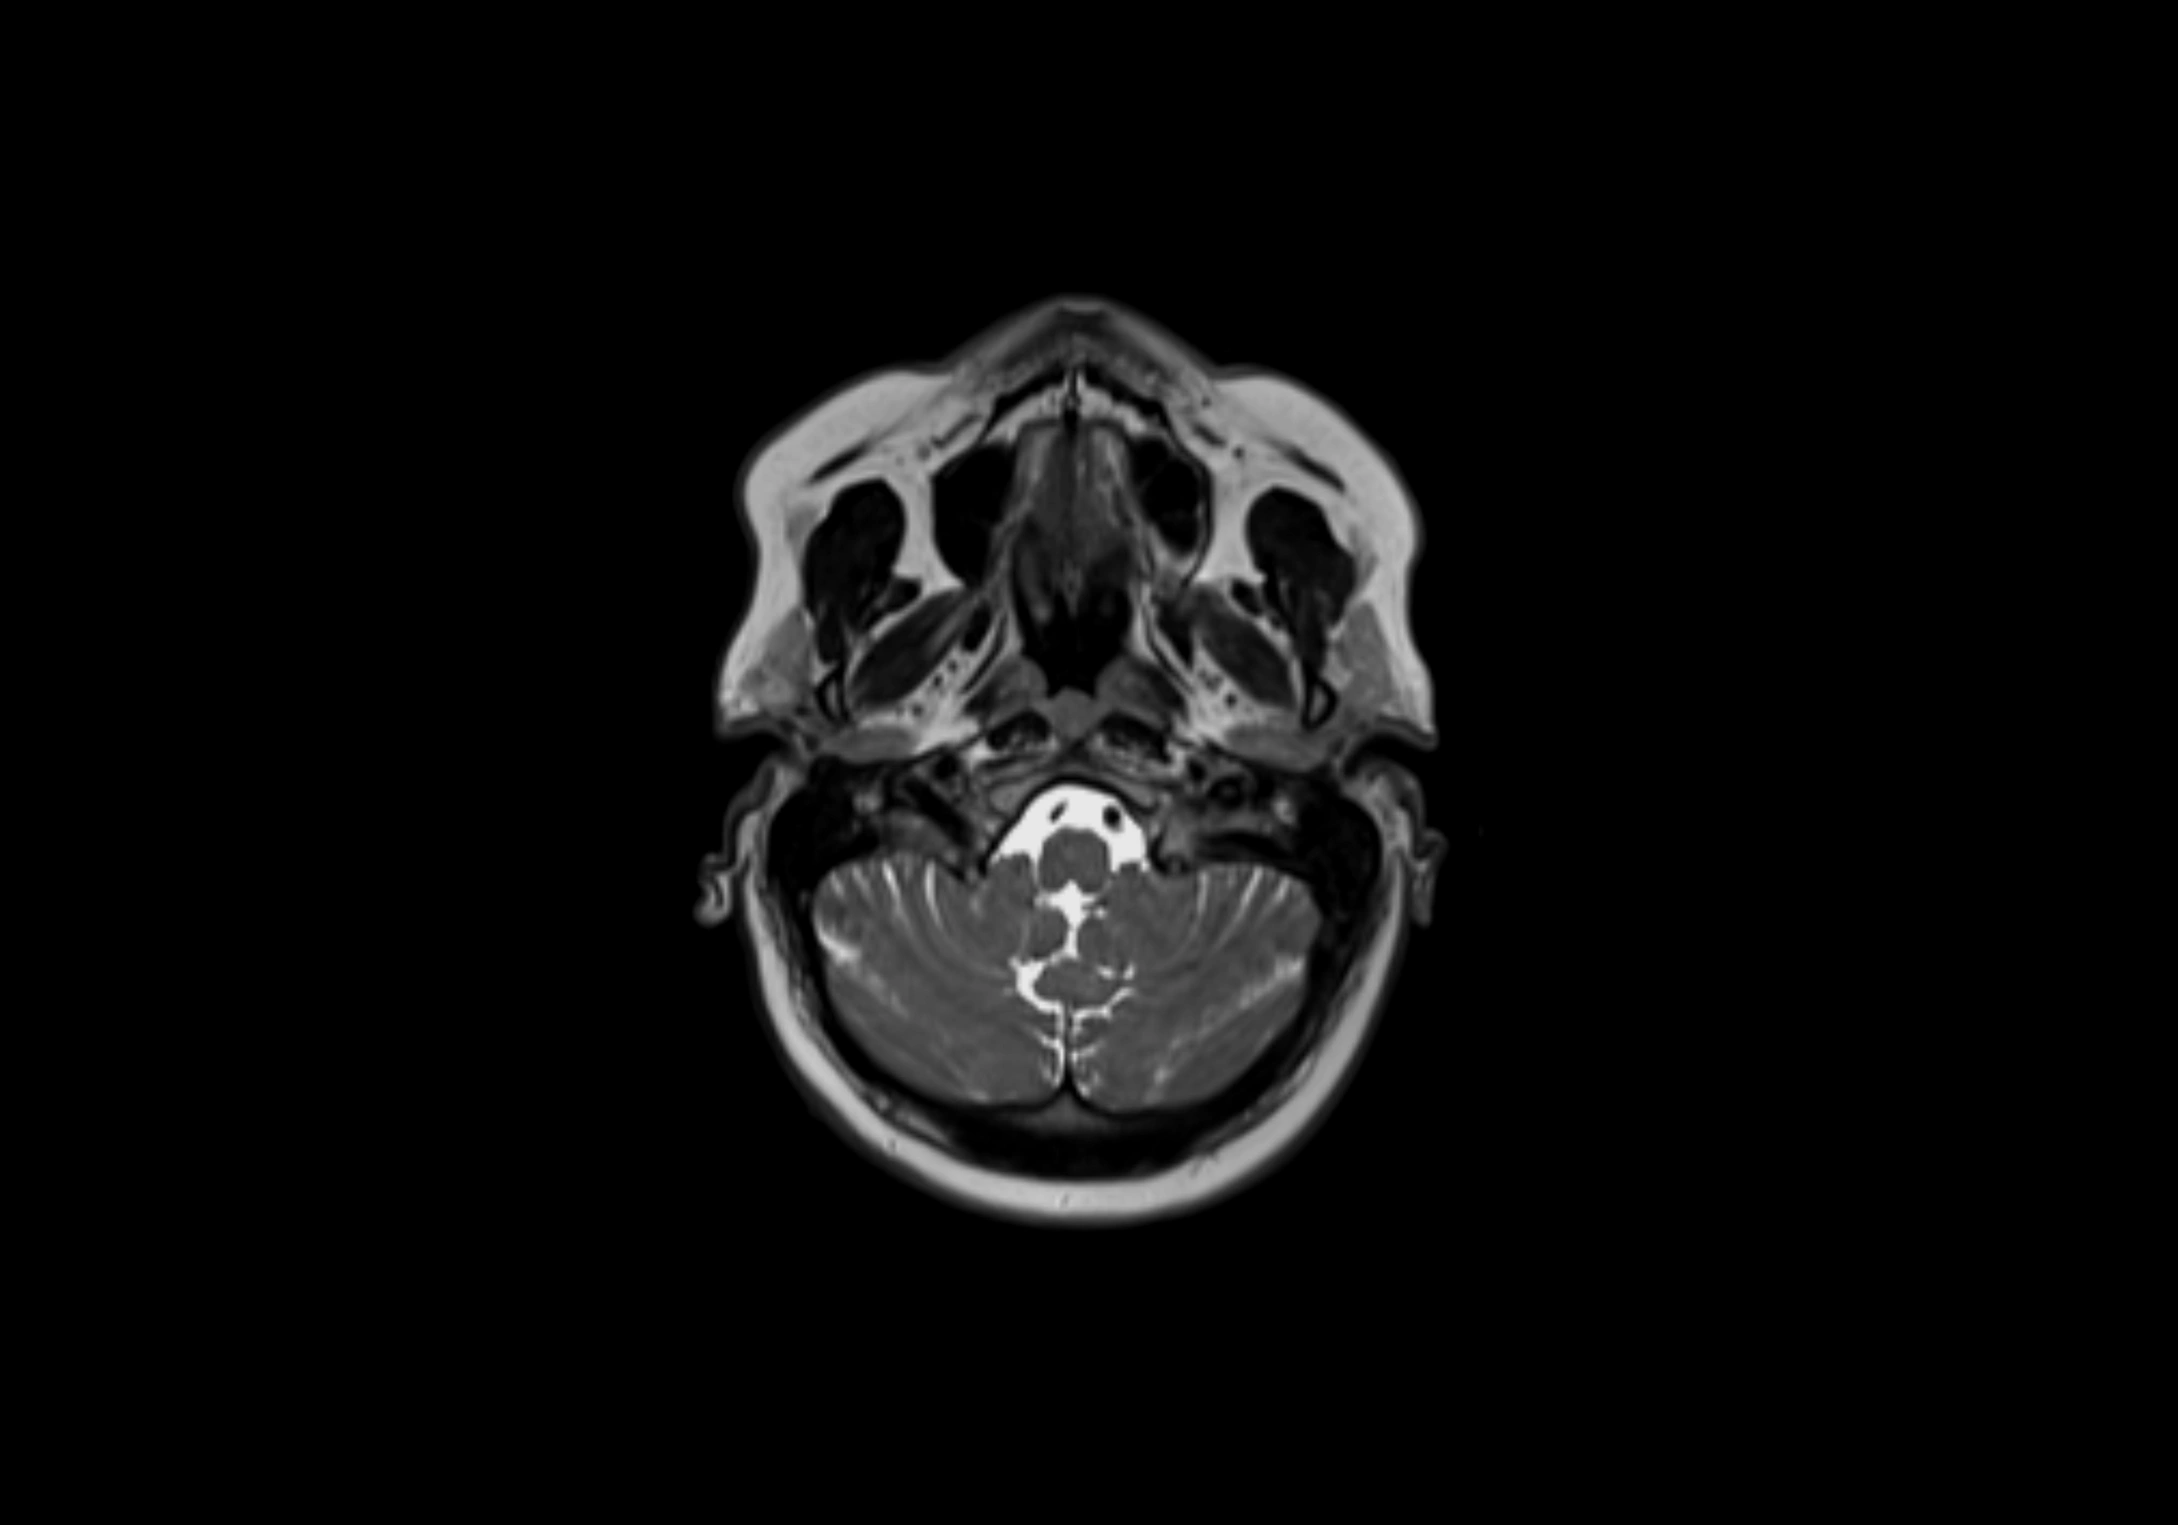

MRI Appearance

T2-weighted images:

• Nodes show intermediate signal, with surrounding fat bright

• Useful for detecting edema, inflammation, or infiltration

• Fatty hilum may appear slightly hyperintense relative to cortex